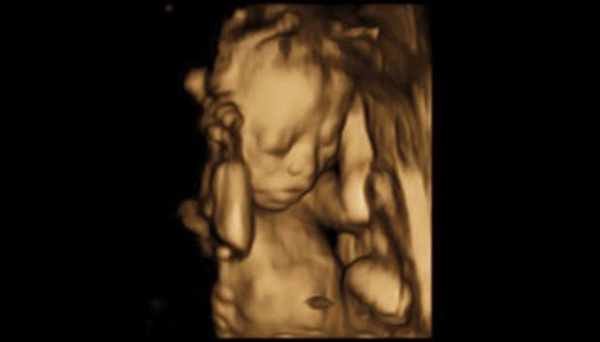

3D/4D Ultrasonography

3D/4D ultrasonography is an advanced imaging technique that provides three-dimensional and real-time (4D) images of the fetus during pregnancy or various organs in the body. Unlike traditional 2D ultrasounds, 3D imaging captures detailed, life-like still images, while 4D allows for live video, capturing movements in real time

This cutting-edge technology is particularly popular in prenatal care, offering expectant parents a glimpse of their unborn baby with stunning clarity. It's also used for more precise diagnosis of structural abnormalities in different parts of the body.